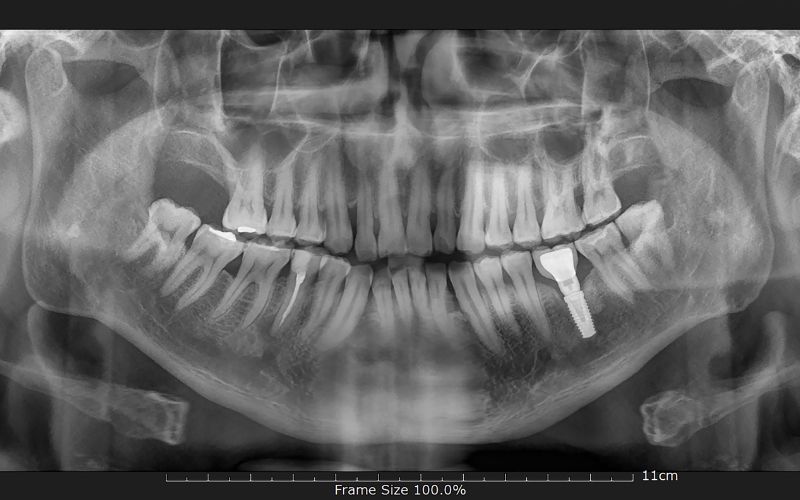

La cirurgia oral i la implantologia dental permeten diagnosticar i tractar quirúrgicament lesions relacionades amb les dents i els maxil·lars. Els implants dentals substitueixen les arrels naturals de les dents perdudes. Solen ser de titani i permeten subjectar corones o ponts que faran la funció de les dents. Així l’objectiu dels implants és funcional i estètic.

Són uns additaments de titani que s’insereix a l’os mitjançant una intervenció quirúrgica. Tenen la funció de crear una arrel artificial. Posteriorment, es col·locarà una pròtesi a sobre que substituirà la dent perduda.

Els implants dentals serveixen per reemplaçar dents perdudes o greument danyades, millorant la funció oral i l’estètica de la boca.